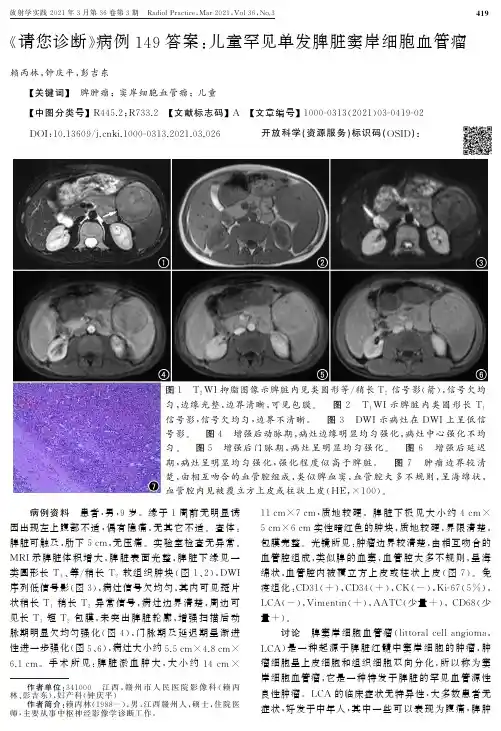

作者单位:341000㊀江西,赣州市人民医院影像科(赖丙林㊁彭吉东),妇产科(钟庆平)作者简介:赖丙林(1988-),男,江西赣州人,硕士,住院医师,主要从事中枢神经影像学诊断工作.«请您诊断»病例149答案:儿童罕见单发脾脏窦岸细胞血管瘤赖丙林,钟庆平,彭吉东ʌ关键词ɔ㊀脾肿瘤;窦岸细胞血管瘤;儿童ʌ中图分类号ɔR 445.2;R 733.2㊀ʌ文献标志码ɔA㊀ʌ文章编号ɔ1000G0313(2021)03G0419G02D O I :10.13609/j.c n k i .1000G0313.2021.03.026㊀㊀㊀㊀开放科学(资源服务)标识码(O S I D ):图1㊀T 2W I 抑脂图像示脾脏内见类圆形等/稍长T 2信号影(箭),信号欠均匀,边缘光整,边界清晰,可见包膜.㊀图2㊀T 1W I 示脾脏内类圆形长T 1信号影,信号欠均匀,边界不清晰.㊀图3㊀DW I 示病灶在DW I 上呈低信号影.㊀图4㊀增强后动脉期,病灶边缘明显均匀强化,病灶中心强化不均匀.㊀图5㊀增强后门脉期,病灶呈明显均匀强化.㊀图6㊀增强后延迟期,病灶呈明显均匀强化,强化程度似高于脾脏.㊀图7㊀肿瘤边界较清楚,由相互吻合的血管腔组成,类似脾血窦,血管腔大多不规则,呈海绵状,血管腔内见被覆立方上皮或柱状上皮(H E ,ˑ100).㊀㊀病例资料㊀患者,男,9岁.缘于1周前无明显诱因出现左上腹部不适,偶有隐痛,无其它不适.查体:脾脏可触及,肋下5c m ,无压痛.实验室检查无异常.M R I 示脾脏体积增大,脾脏表面光整,脾脏下缘见一类圆形长T 1㊁等/稍长T 2软组织肿块(图1㊁2),DW I 序列低信号影(图3),病灶信号欠均匀,其内可见斑片状稍长T 1稍长T 2异常信号,病灶边界清楚,周边可见长T 1短T 2包膜,未突出脾脏轮廓,增强扫描后动脉期明显欠均匀强化(图4),门脉期及延迟期呈渐进性进一步强化(图5㊁6),病灶大小约5.5c mˑ4.8c mˑ6.1c m .手术所见:脾脏淤血肿大,大小约14c mˑ11c mˑ7c m ,质地较硬.脾脏下极见大小约4c mˑ5c mˑ6c m 实性暗红色的肿块,质地较硬,界限清楚,包膜完整.光镜所见:肿瘤边界较清楚,由相互吻合的血管腔组成,类似脾的血窦,血管腔大多不规则,呈海绵状,血管腔内被覆立方上皮或柱状上皮(图7).免疫组化:C D 31(+),C D 34(+),C K (-),K i G67(5%),L C A (-),V i m e n t i n (+),A A T C (少量+),C D 68(少量+).讨论㊀脾窦岸细胞血管瘤(l i t t o r a l c e l l a n gi o m a ,L C A )是一种起源于脾脏红髓中窦岸细胞的肿瘤,肿瘤细胞呈上皮细胞和组织细胞双向分化,所以称为窦岸细胞血管瘤,它是一种特发于脾脏的罕见血管源性良性肿瘤.L C A 的临床症状无特异性,大多数患者无症状,好发于中年人,其中一些可以表现为腹痛,脾肿大,脾功能亢进和疼痛等.L C A的影像学表现可分为多发结节型和单发结节型.多发结节型C T平扫表现为多发大小不等的类圆形低密度结节,可呈弥漫性分布,可伴脾脏不同程度肿大,密度均匀,当部分病灶较大时,密度不均匀,无包膜及钙化,大部分病灶边界清楚[1G2].在M R上,T1W I多呈等或稍低信号,边界欠清;T2W I表现为稍高信号,信号可不均匀,部分病变内可因含铁血黄素沉积而呈低信号,呈 雀斑征 ,但该特征性表现与组织中含铁血黄素的含量有关[3].增强扫描动脉期表现为由周边向中心缓慢环形的渐进性强化模式,静脉期逐渐向中心强化,延迟期表现多样,可呈稍低或等密度/信号,主要与病灶大小不等㊁相互吻合窦状腔隙的数量㊁大小㊁吻合程度㊁瘤体内纤维组织含量或血管成分有关[1].单发结节型大多数边缘清楚,密度/信号均匀,结节体积多数较大,长径常>3c m,脾脏体积不大或仅局部增大,增强动脉期可见环形明显强化,门脉期进一步强化,强化趋于均匀,延迟期密度/信号略高于脾实质[4].参考文献:[1]㊀程冰雪,周莉,杨晨等.脾窦岸细胞血管瘤C T表现及多样强化方式特点分析[J].临床放射学杂志,2019,38(7):1229G1233.[2]㊀薛红红,白宝艳,王胜利.脾脏窦岸细胞血管瘤的超声造影表现与病理对照[J].中国医学影像学杂志,2017,25(1):11G12.[3]㊀丁莺,曾蒙苏,饶圣祥,等.脾脏窦岸细胞血管瘤的M R I表现及与病理对照分析[J].放射学实践,2012,27(7):761G764.[4]㊀蔡勇时,左敏,龚静山,等.孤立性脾窦岸细胞血管瘤一例[J].临床放射学杂志,2019,38(3):568G569.(收稿日期:2020G12G01㊀修回日期:2020G12G28)欢迎订阅2021年«放射学实践»㊀㊀«放射学实践»是由国家教育部主管,华中科技大学同济医学院主办,与德国合办的全国性影像学学术期刊,创刊至今已36周年.遵照同行评议㊁价值导向㊁等效应用原则,国内各大学会㊁协会㊁组织机构通过科技工作者推荐㊁专家评议㊁结果公示等规定程序,«放射学实践»杂志入选中国科协发布10大领域«我国高质量科技期刊分级目录»业内认可的较高水平期刊.2018年8月,«放射学实践»杂志再次入选北京大学和北京高校图书馆期刊工作研究会共同主持的国家社会科学基金项目 学术期刊评价及文献计量学研究 研究成果 «中国核心期刊要目总览».这是继1999年之后的第5次入选临床医学/特种医学类核心期刊.本刊坚持服务广大医学影像医务人员的办刊方向,关注国内外影像医学的新进展㊁新动态,全面介绍X线㊁C T㊁磁共振㊁介入放射及放射治疗㊁超声诊断㊁核医学㊁影像技术学等医学影像方面的新知识㊁新成果,受到广大影像医师的普遍喜爱.本刊为国家科技部中国科技论文核心期刊㊁中国科学引文数据库统计源期刊,在首届«中国学术期刊(光盘版)检索与评价数据规范»执行评优活动中,被评为«C A J C D规范»执行优秀期刊.主要栏目:论著㊁继续教育园地㊁专家荐稿㊁研究生展版㊁图文讲座㊁本刊特稿㊁实验研究㊁传染病影像学㊁影像技术学㊁外刊摘要㊁学术动态㊁请您诊断㊁病例报道㊁知名产品介绍㊁信息窗等.本刊为月刊,每册25元,全年定价300元.国内统一刊号:I S S N1000G0313/C N42G1208/R㊀㊀邮政代号:38G122电话:(027)69378385EGm a i l:f s x s j z z@163.c o m㊀㊀网址:h t t p://w w w.f s x s j.n e t编辑部地址:430199㊀武汉市蔡甸区中法新城同济医院专家社区别墅C栋。